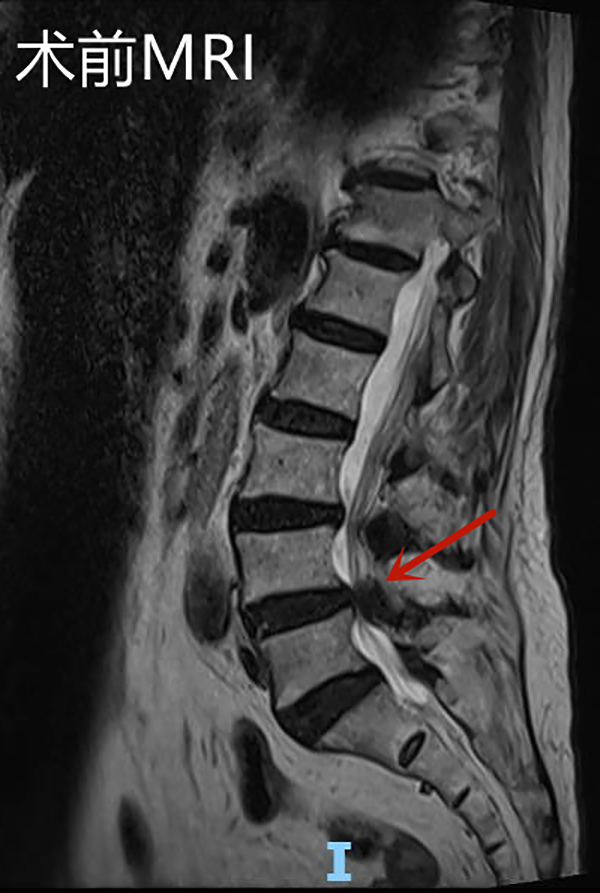

邱奶奶入院后查腰椎磁共振顯示L4/5椎管嚴(yán)重狹窄,神經(jīng)根受壓,明確診斷為腰椎管狹窄癥。腰椎骨狹窄癥是老年人群常見(jiàn)的腰椎退行性疾病。狹窄可以發(fā)生在中央椎管、側(cè)隱窩以及椎間孔等部位,由于椎管或神經(jīng)根管的狹窄,致使椎管內(nèi)神經(jīng)受壓,神經(jīng)功能障礙,可表現(xiàn)為腰痛、下肢疼痛或麻木,隨著病情的發(fā)展可出現(xiàn)下肢運(yùn)動(dòng)及感覺(jué)障礙。

手術(shù)后復(fù)查腰椎MRI顯示:相應(yīng)的椎管狹窄及神經(jīng)根壓迫已解除,手術(shù)后第2天邱奶奶便可下地行走,腰痛及左下肢疼痛緩解,復(fù)查腰椎磁共振見(jiàn)L4/5左側(cè)狹窄已完全解除。手術(shù)后第4天,患者順利出院,沒(méi)有出現(xiàn)任何手術(shù)并發(fā)癥。